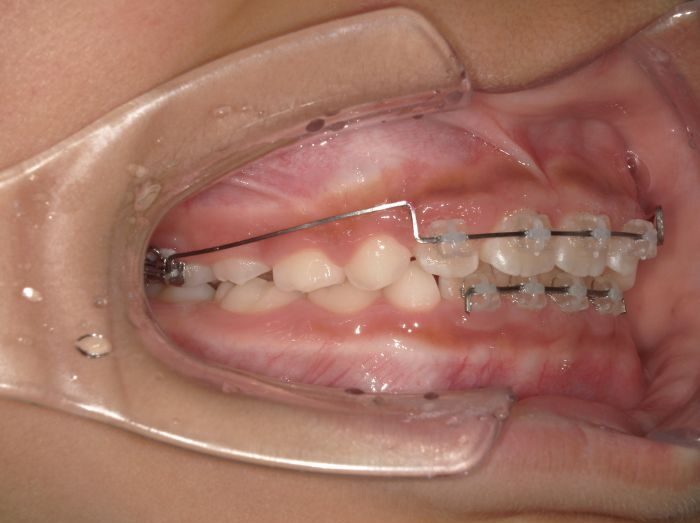

2×4

(ツーバイフォー)上下の前歯に4本ずつ、奥歯に2本、合計12本の永久歯にブラケットを装着し、部分的に歯並びを整える治療法です。乳歯が残っている時期に行う「準備矯正」として使用され、歯並びや咬み合わせの基礎を作ります。

フルパッシブ矯正

永久歯がすべて生えそろった中学生以降に行う、本格的な矯正治療です。ワイヤーを「やさしく固定」する特殊な装置を使用し、歯に強い力をかけずに自然な動きを促します。